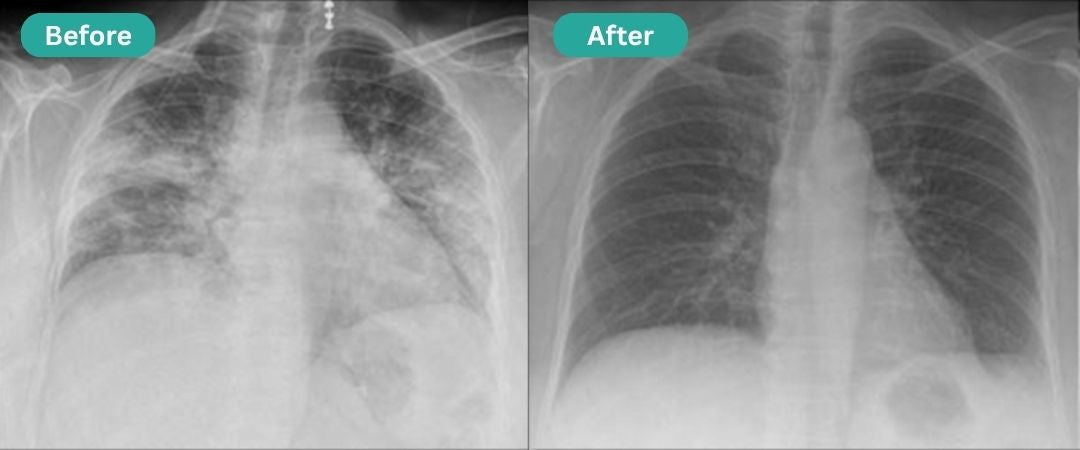

Help me recover Lungs after smoking

After quitting smoking, my lungs felt weak. Breathexa helped me rebuild stamina in just 4 weeks!

—Mark D., Chicago, IL

Results From Over 5,000 User Surveys